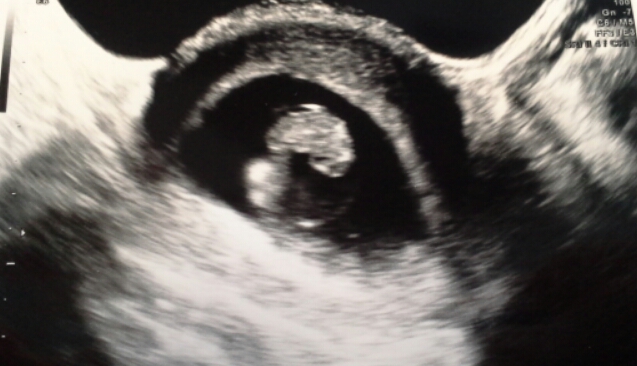

We went in yesterday for our 2nd ultrasound (first was at 5 weeks - only saw gestational sac) I thought I was about 7 weeks, but we found out yesterday that I am measuring 8 weeks! Baby is doing great with a heart beat of 164BPM! So excited that this is finally felling real, and making my horrible symptoms worth it!

I'm officially due April 12, 2016!